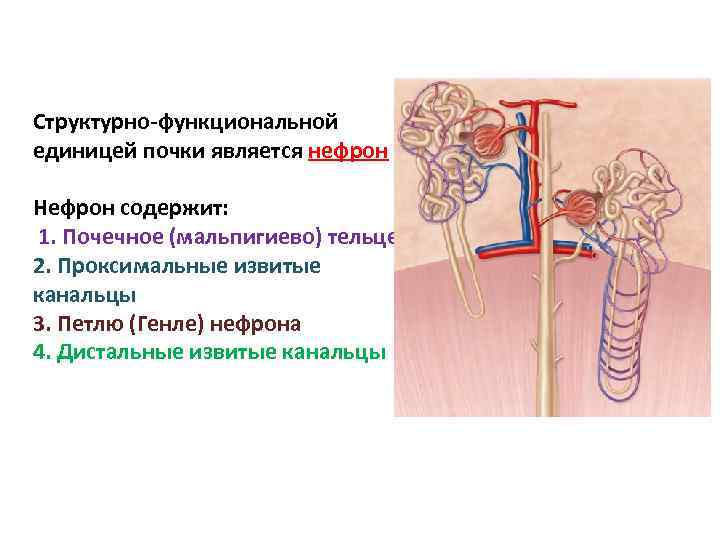

Структурно-функциональной единицей почки является нефрон Нефрон содержит: 1. Почечное (мальпигиево) тельце 2. Проксимальные извитые канальцы 3. Петлю (Генле) нефрона 4. Дистальные извитые канальцы

Структурно-функциональной единицей почки является нефрон Нефрон содержит: 1. Почечное (мальпигиево) тельце 2. Проксимальные извитые канальцы 3. Петлю (Генле) нефрона 4. Дистальные извитые канальцы

Далее собирательная трубочка, затем сосочковые протоки, открывающиеся на верхушке пирамид сосочковыми отверстиями

Далее собирательная трубочка, затем сосочковые протоки, открывающиеся на верхушке пирамид сосочковыми отверстиями

Почечное (мальпигиево) тельце состоит из капсулы клубочка (Шумлянского. Боумена) и капиллярной сети

Почечное (мальпигиево) тельце состоит из капсулы клубочка (Шумлянского. Боумена) и капиллярной сети